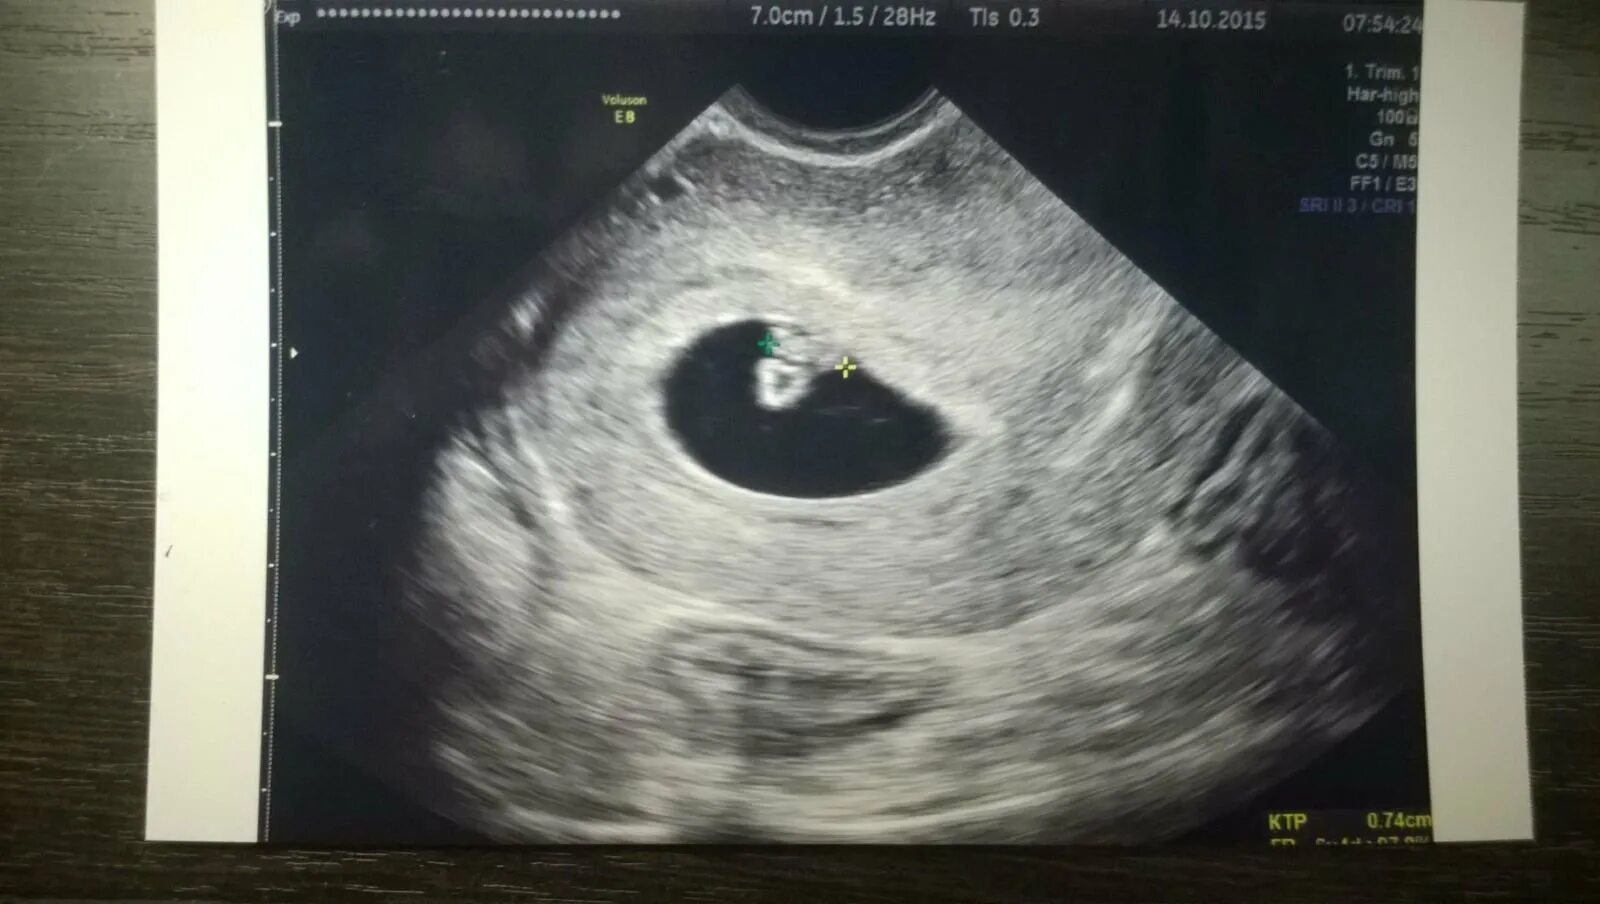

Как выглядит 5 дней беременности